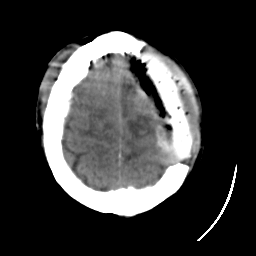

Meningioma: Roentgen-ray CT #1 -- Slice #19

[Home][Help][Clinical] Slice 19